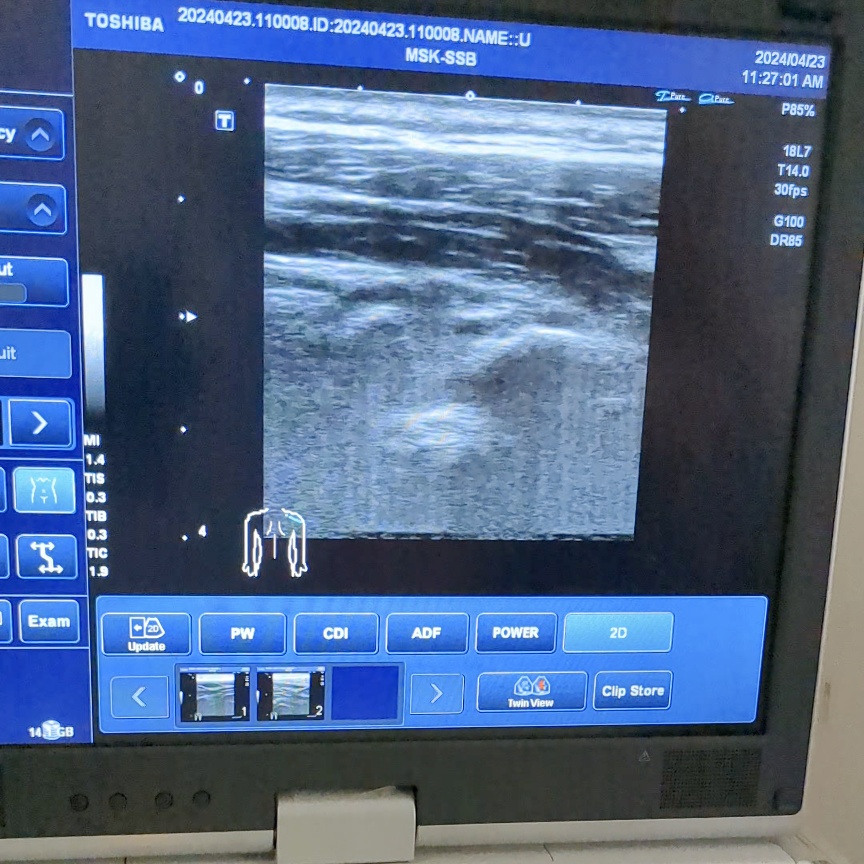

肩こりのエコー画像

当院ではエコーも活用しながら、筋肉や運動器の状態を確認し、状態の把握に努めています。